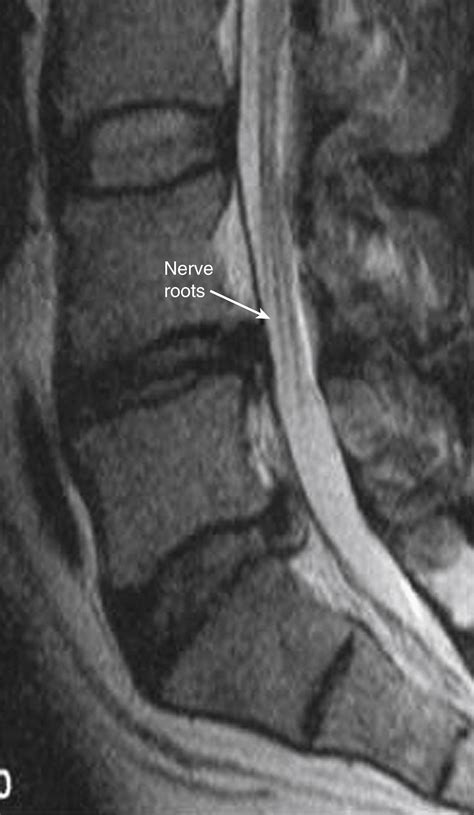

Mri Nerve Roots Lumbar Disc Sequestration Mimicking A Tumor: Report Of

Axial Cross-section Of Lumbar Spine At L4-L5 With Posterior-lateral